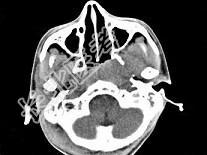

- 单项选择题男,17岁, 自诉鼻涕中带血3个月,伴耳闷、听力减退, 无发热。如图所示鼻咽部病灶最可能的诊断为 ( )

C、鼻咽癌